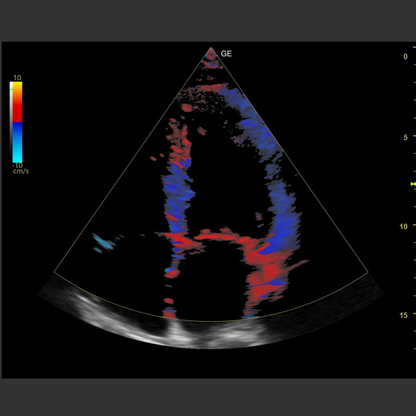

GE Ultraschall Versana Balance

Produktbeschreibung

Produktmerkmale

- Versana Balance V2

- Linearschallkopf L6-12-RS

- Convexschallkopf 4C-RS